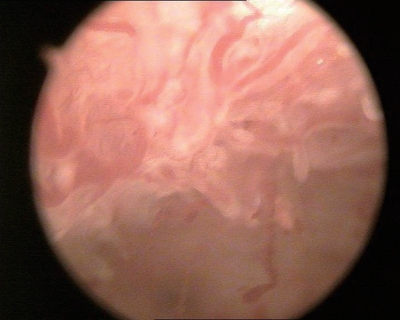

③分泌期子宫内膜:内膜往往呈半球状或息肉样突起,水肿样改变,半透明白色或黄白色,可清晰透见毛细血管网,皱褶减少变浅,腺体开口难辨(图3-7)。